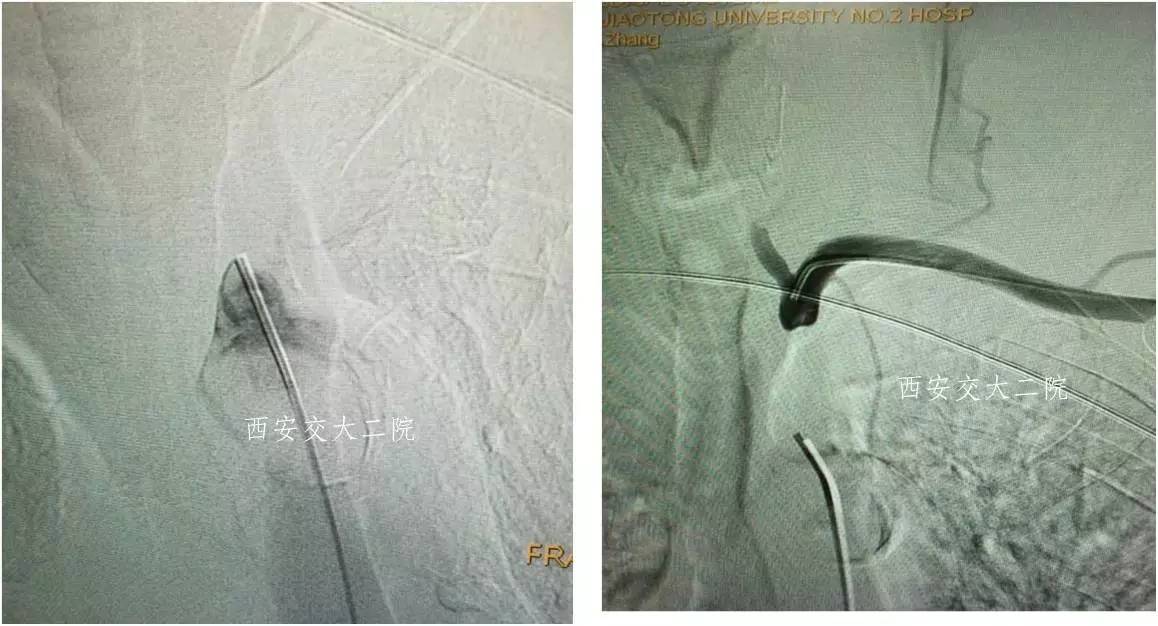

Case 1 左锁骨下慢性闭塞再通(2013年)

》男,75岁,头晕4年。

》DSA见左侧椎动脉起始闭塞,左侧锁骨下从右侧椎动脉血盜。

Case 2 右侧锁骨下动脉慢性闭塞再通术

》58岁,男;

》头晕、右上肢乏力4年,活动后明显;

》查体:右上肢皮温低,右侧桡动脉搏动弱,右上肢血压测不到。

Case 3 左锁骨下慢性闭塞再通(2015年)

》男,80岁,活动后头晕7年。

》5年前外院脑DSA发现左侧锁骨下动脉闭塞,右侧椎动脉开口狭窄,给予右侧椎动脉开口支架成形术,术后头晕稍有减轻,但活动后仍头晕,不能跳舞,患者坚决要求治疗。